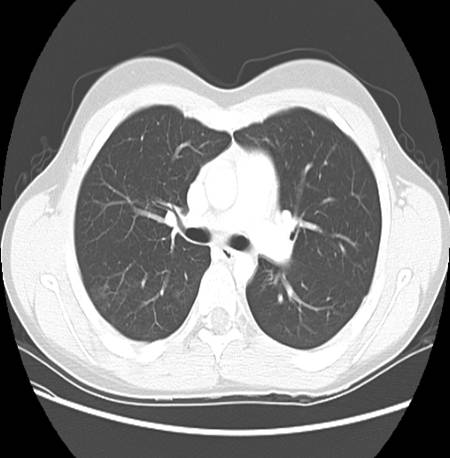

A CT chest was also ordered to further characterize the pulmonary involvement.

Describe chest CT.